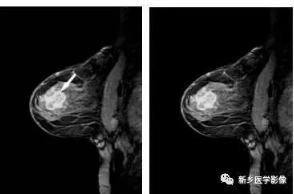

图 乳腺常见病变的mri表现 乳腺肿瘤学 天山医学院

图 乳腺恶性疾病 特殊形式的乳腺癌的mri表现 乳腺肿瘤学 天山医学院

图 乳腺其他恶性肿瘤的mri表现 乳腺肿瘤学 天山医学院